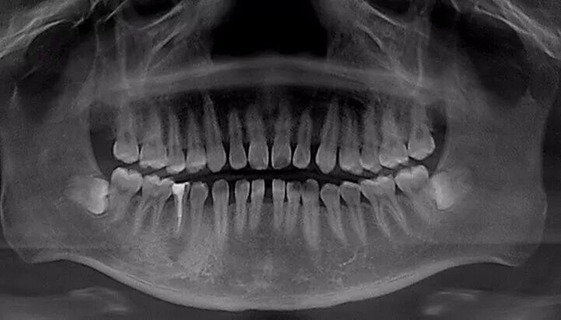

牙缝问题从片子里可以看得很明显了。